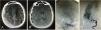

ResultsMedian age was 51 years and 48% (12/25) were females. At their arrival, 76% (19/25) presented decreased level of consciousness and 55.55% (10/18) neurological deficits. Aneurysmal location was left MCA in 57.14% (8/14) and MCA segments were M4 in 76.92% (10/13) and bifurcation in 23.07% (3/13), median aneurysmal size was 6 mm, median hematoma size was 10 mm, median midline shift was 9 mm, aneurysmal projection and MCA concavity were anterior in 100% (3/3), subarachnoid hemorrhage (SAH) was present in 52.17% (12/23). The treatment was surgery in 84% (21/25), endovascular in 12% (3/25) and in 20% (5/25) decompressive craniectomy (DC) was necessary. Glasgow Outcome Scale (GOS) was >3/favorable in 66.66% (16/24) and death in 16.66% (4/2).

ConclusionsAnterior MCA concavity and aneurysmal projection might be related with aSDH presentation in proximal MCA aneurysms. We should suspect aneurysm origin when there is no history or stigma of trauma, and CT shows disproportionately massive aSDH. Hematoma evacuation solves the compressive mechanism which is the main cause of neurological deterioration in pure aSDH cases, because of that, immediate hematoma evacuation could justify better outcome in these patients.